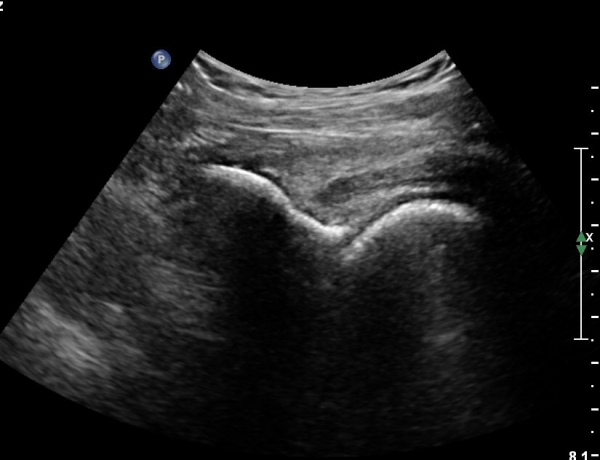

[¾ûµ¢ÀÌ] ÀüÇÏÀå°ñ±Ø °ß¿­°ñÀý(avulsion fracture of anterior inferior iliac spine)

Ç㸮¿Í ¾ûµ¢ÀÌ ÅëÁõ°ú ¿ìÃø ´Ù¸® ¶¯±è (±ÝÀÏ)

±ÝÀÏ ³Ñ¾îÁø ÈÄ ¸ñ, Ç㸮, ´Ù¸®ÀÇ ÅëÁõÀÌ ¹ß»ý. °ÉÀ» ¶§ ´Ù¸®°¡ ¾Èµé¸°´Ù.

´Éµ¿Àû SLR ¾ÈµÊ. ÀúÇ׿¡ ´ëÇÑ °í°üÀý ±¼°î°ú ¹«¸­ ½ÅÀü ½Ã ÅëÁõ°ú ±Ù¾àÁõÀ» º¸ÀÓ.